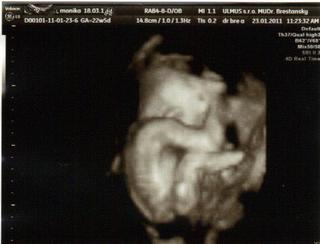

dnes sme boli na tom 4D... no naša malá potvora sa nám ukázala iba na malinkú chvíľočku a potom ani za nič 😀

Malinká je krásna a váži cca 572 g 😀 Zodpovedáme 23 tt a 2 d.. sme 22 tt a 5 d... takže je to ok 🙂

STále mala ručičku pred tváričkou 😀